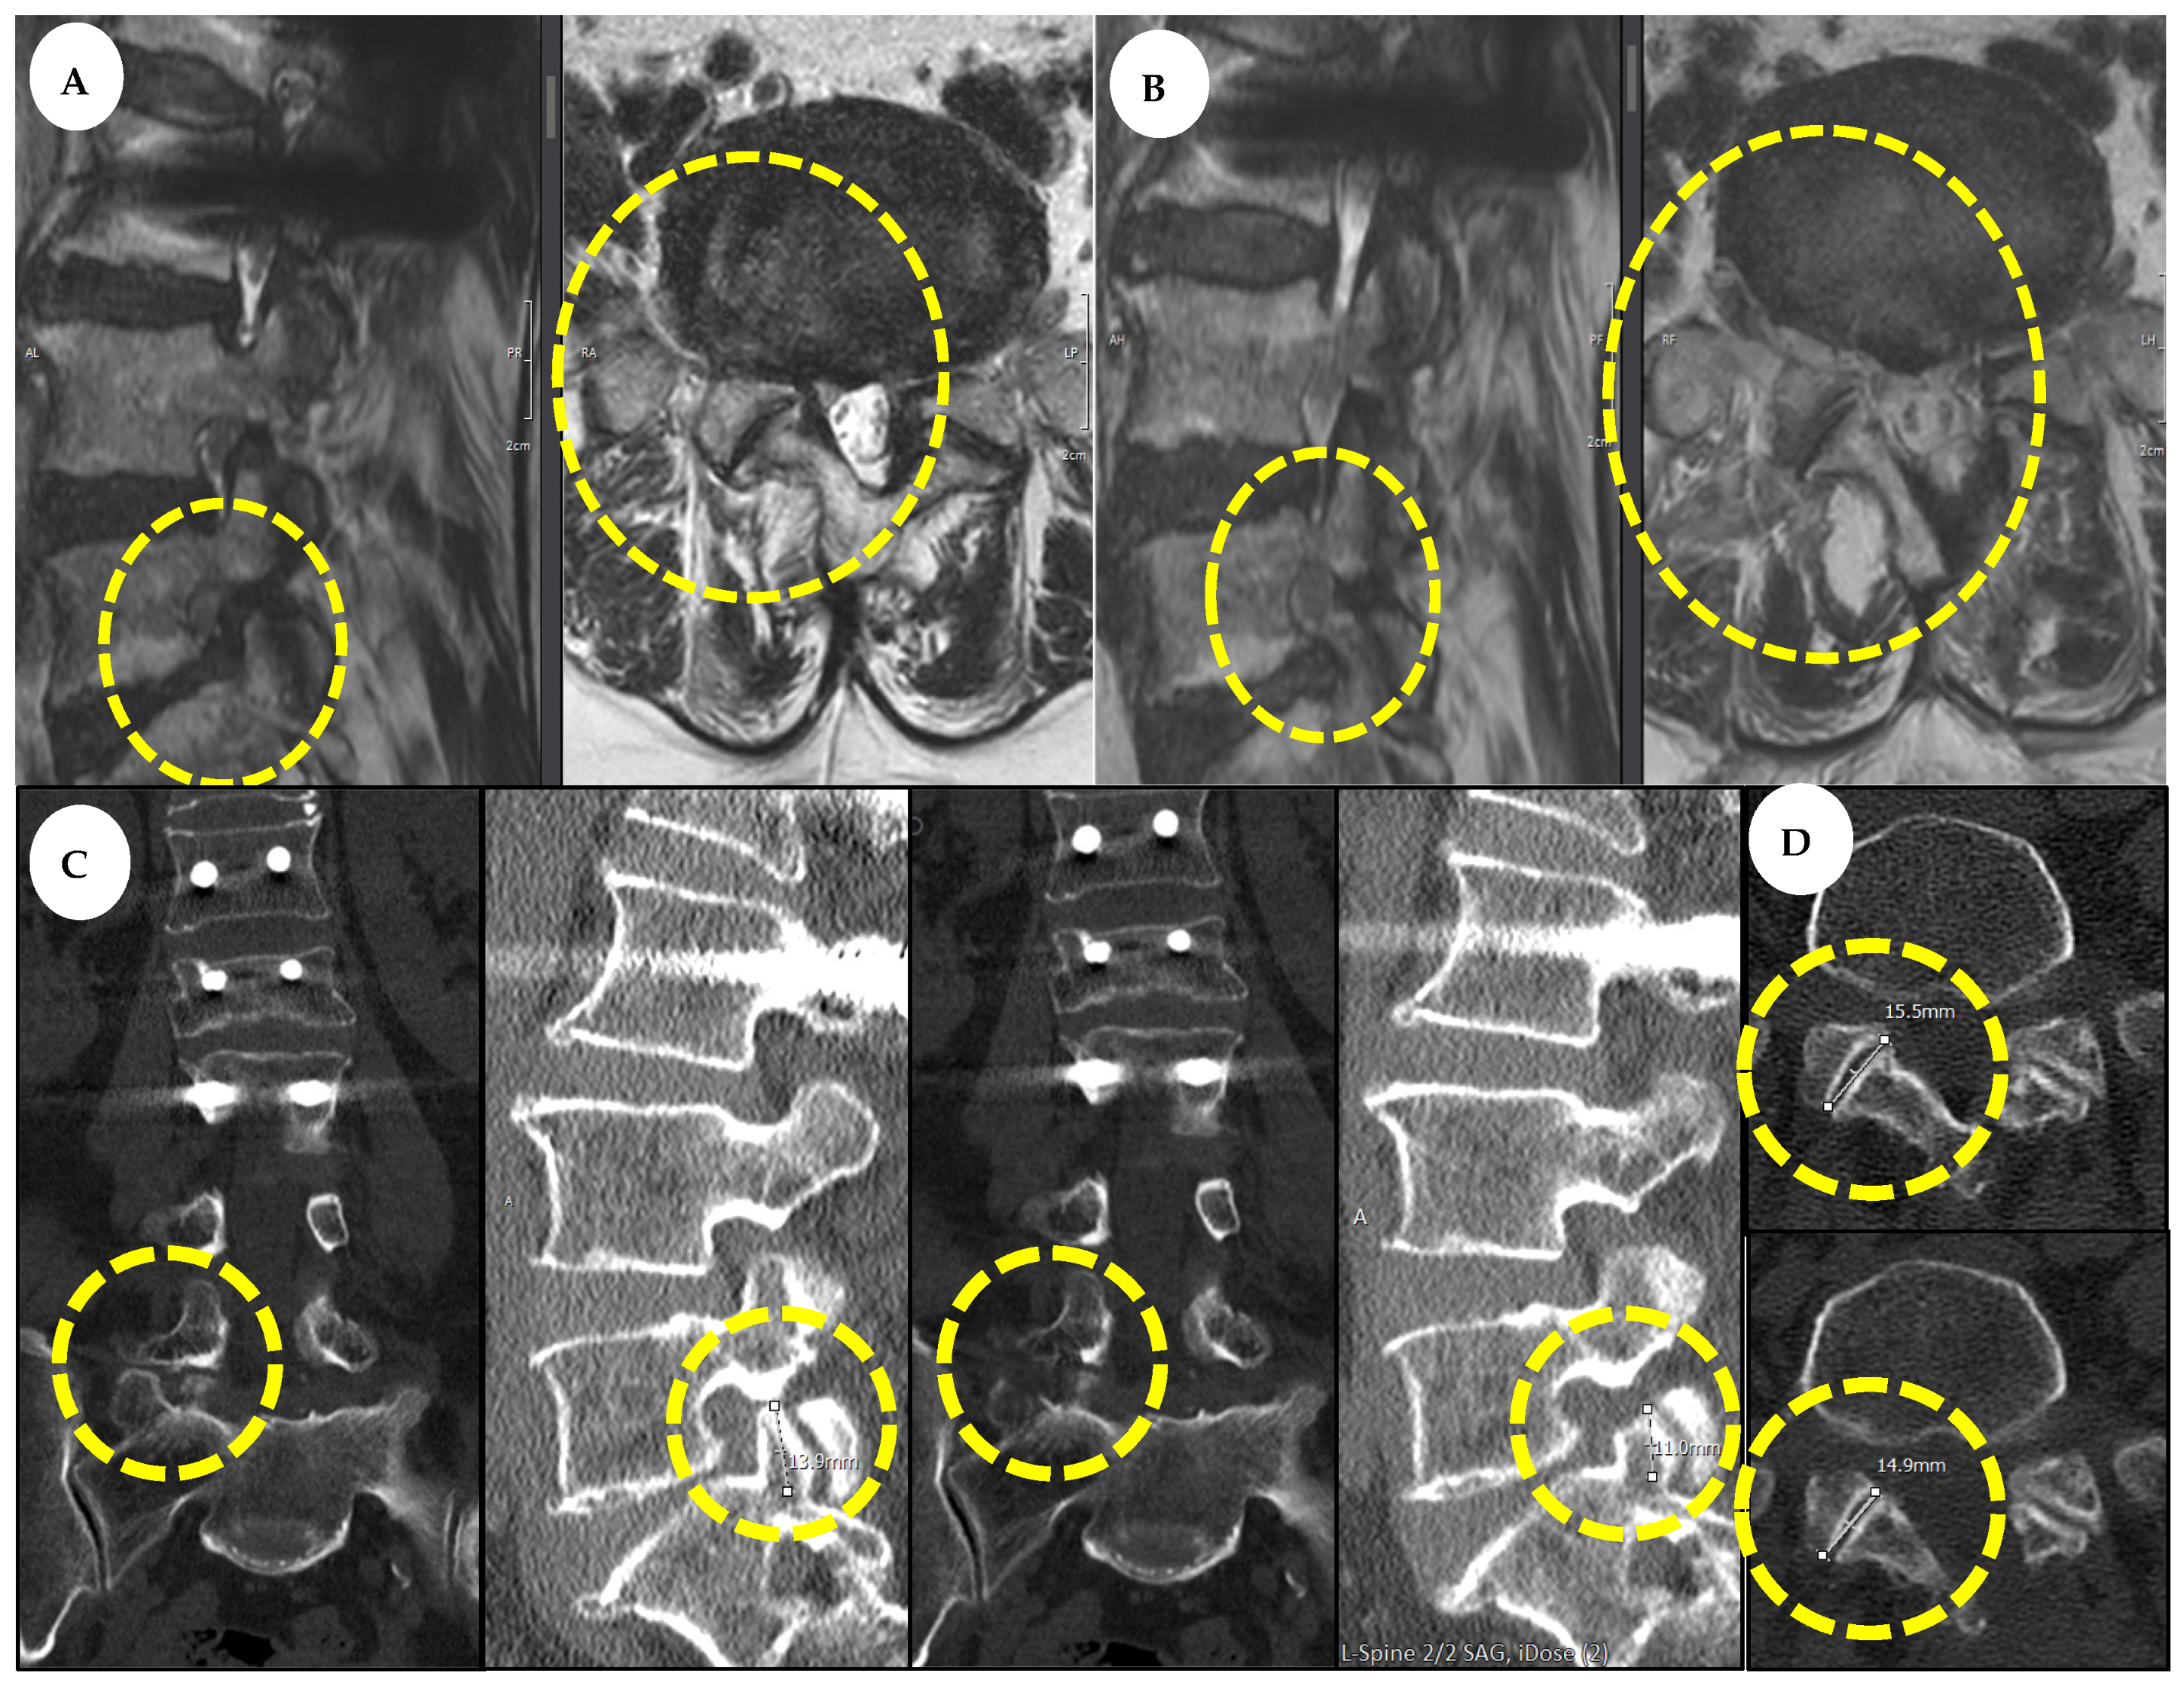

3.5. Case Report

3.3. Evaluation of Radiological Outcomes

| Facet joint length (mm) | 13.57 ± 1.34 | 12.22 ± 1.48 | 90.05% |

| SAP length (mm) | 11.74 ± 1.14 | 8.87 ± 1.25 | 75.55% |